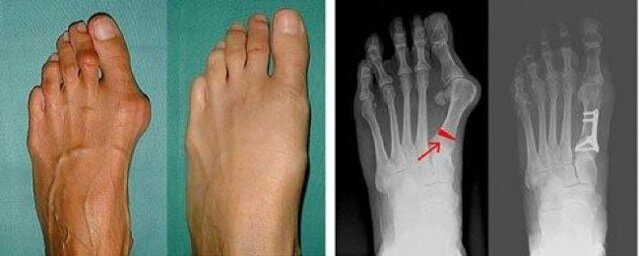

Hallux valgus (HV) – латинское обозначение вальгусной деформации I-го пальца стопы, та самая “шишка на стопе” или “косточка на ноге” у многих женщин. Данное заболевание чаще всего наследственное и преимущественно поражает женщин (около 90% пациентов). Других причин у этой деформации достаточно много. Это и травмы и инфекции, а также последствия артрозов и артритов различного происхождения. Ношение “неправильной”, с ортопедической точки зрения обуви, также развивает или способствует развитию болезни.